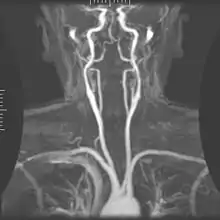

Angiografie prin rezonanță magnetică

![]() Artera carotidă externă izvorând din arteră carotidă comună și alimentând cu sânge structurile feței și gâtului | |